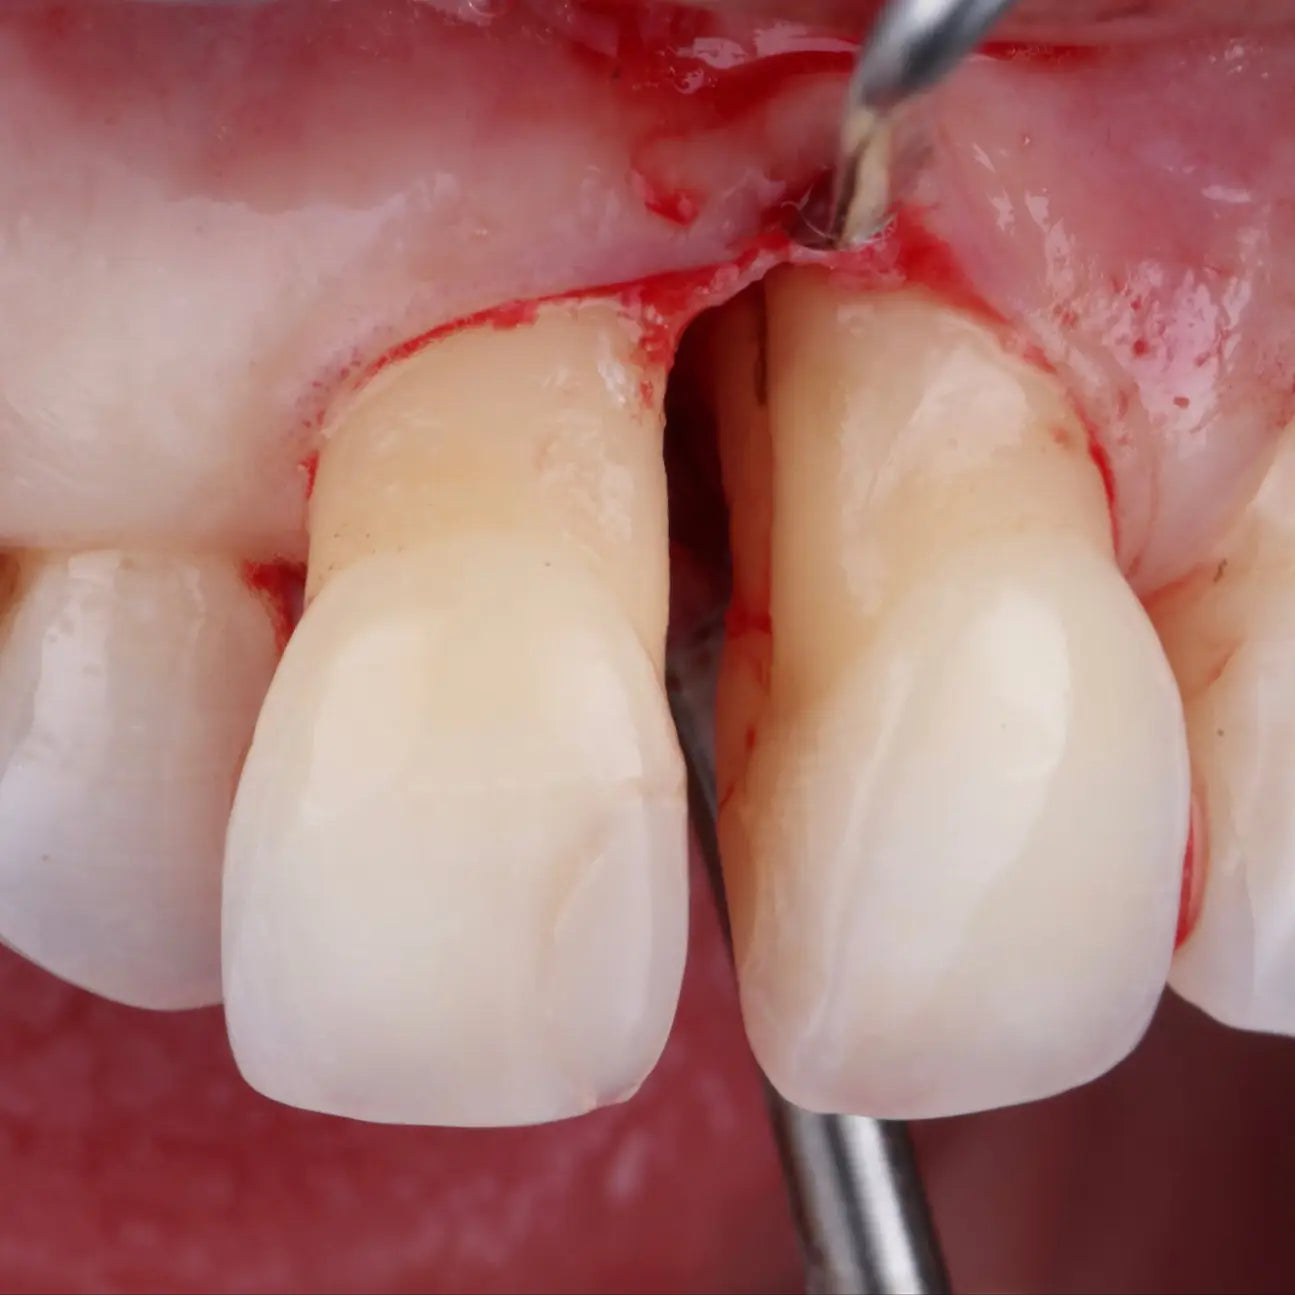

Les aspects du traitement chirurgical des défauts infra-osseux

Elle vise également à approfondir le choix des comblements et des substituts selon les indications cliniques, ainsi qu’à maîtriser les différentes incisions (m-MIST, SFA, EPP...) afin d’optimiser la cicatrisation parodontale.